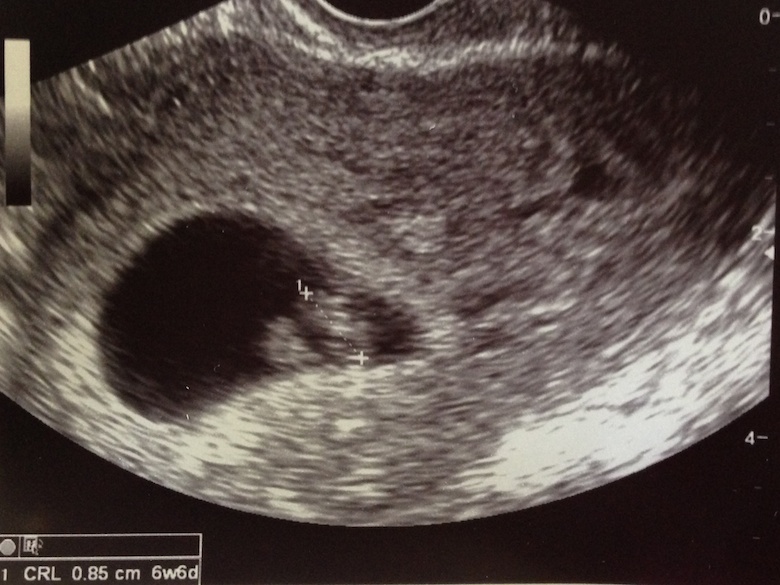

블로그 자주 써야지라고 블로그에 써놓고 블로그 안쓰면 좀 웃기지 않을까 했는데 어쩔 수 없이 뭔가 적어야할 것 같은 경우가 생겼습니다. 이제부터 본격 임신 / 출산 / 육아 블로그를! 참, 예정일은 10월 6일. 이제 7주차인데, 확실히 경험이 없는 친구들은 바로, 남자냐…